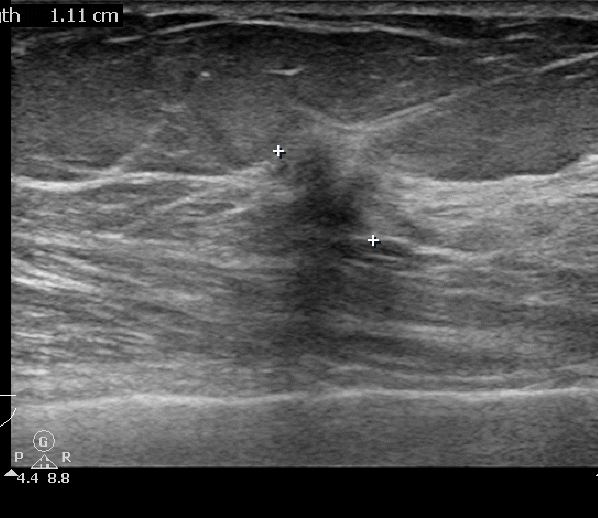

외부검사상 이상소견으로 내원하신 60대 여성분으로

우측유방의 의심스러운 혹 조직검사 시행 후 유방암 진단되었읍니다